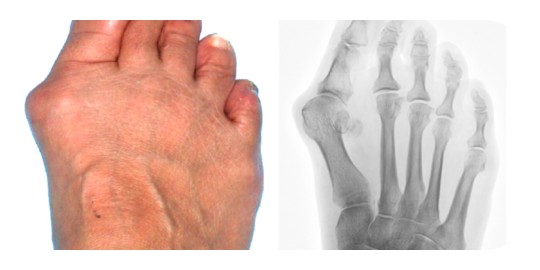

๋ฌด์ง€์™ธ๋ฐ˜์ฆ์€ ์ฒซ ๋ฒˆ์งธ ์—„์ง€๋ฐœ๊ฐ€๋ฝ์ด ๋ฐœ ๋ฐ”๊นฅ์ชฝ์œผ๋กœ ๋ณ€ํ˜•๋˜๋Š” ์ฆ์ƒ์„ ๋งํ•œ๋‹ค. ์—„์ง€๋ฐœ๊ฐ€๋ฝ์€ ๋ฐ”๊นฅ์ชฝ์œผ๋กœ ๊ณผ์ž‰ ๋ณ€ํ˜•๋˜๋ฉด์„œ ๋‘ ๋ฒˆ์งธ ๋ฐœ๊ฐ€๋ฝ ๊ด€์ ˆ๊ณผ ์‚ฌ์ด๊ฐ€ ๋ฉ€์–ด์ง€๊ฒŒ ๋œ๋‹ค. ์ฒซ ๋ฒˆ์งธ ๋ฐœ๊ฐ€๋ฝ ๋จธ๋ฆฌ๋ถ€์˜ ๋‚ด์ธก ๋น„๋Œ€์™€ ๋‹ค๋ฅธ ๋ฐœ๊ฐ€๋ฝ์—๋„ ๋ณ€ํ˜•์ด ๋™๋ฐ˜๋˜๋Š” ๋ณตํ•ฉ์ ์ธ ์งˆํ™˜์ด๋‹ค.

๋ฌด์ง€์™ธ๋ฐ˜์ฆ์˜ ๊ฐ€์žฅ ํ”ํ•œ ์ฆ์ƒ์€ ์ œ1์ค‘์กฑ ๋ฐœ๊ฐ€๋ฝ ๊ด€์ ˆ ์•ˆ์ชฝ ๋Œ์ถœ๋ถ€์˜ ํ†ต์ฆ์ด๋‹ค. ์ด์ฐจ์ ์œผ๋กœ๋Š” ๋‘ ๋ฒˆ์งธ ๋˜๋Š” ์„ธ ๋ฒˆ์งธ ๋ฐœ๊ฐ€๋ฝ์˜ ๋ฐœ๋ฐ”๋‹ฅ ์ชฝ์— ๊ตณ์€์‚ด์ด ์ƒ๊ธด๋‹ค. ๋˜ํ•œ ์‹ ๋ฐœ์˜ ์ž๊ทน์œผ๋กœ ํ”ผ๋ถ€๊ฐ€ ๋‘ํ„ฐ์›Œ์ง€๊ณ  ํ†ต์ฆ์„ ๋™๋ฐ˜ํ•œ ์—ผ์ฆ์ด ์ƒ๊ธฐ๊ธฐ๋„ ํ•˜๋ฉฐ ์ˆ˜์‹œ๋กœ ์‹ ๊ฒฝ์„ ์ž๊ทนํ•ด ์ €๋ฆฐ ์ฆ์ƒ์„ ์œ ๋ฐœํ•˜๊ธฐ๋„ ํ•œ๋‹ค. ์‹ฌํ•œ ๊ฒฝ์šฐ๋Š” ๋‘ ๋ฒˆ์งธ ๋ฐœ๊ฐ€๋ฝ์ด ์—„์ง€๋ฐœ๊ฐ€๋ฝ๊ณผ ๊ฒน์ณ์ง€๊ฑฐ๋‚˜ ๊ด€์ ˆ์ด ํƒˆ๊ตฌ๋˜๊ธฐ๋„ ํ•˜๊ณ , ์ƒˆ๋ผ๋ฐœ๊ฐ€๋ฝ ์ชฝ์— ๊ด€์ ˆ์ด ๋Œ์ถœ๋˜๋Š” ๋ณ€ํ˜•์ด ์ƒ๊ธฐ๊ธฐ๋„ ํ•œ๋‹ค.